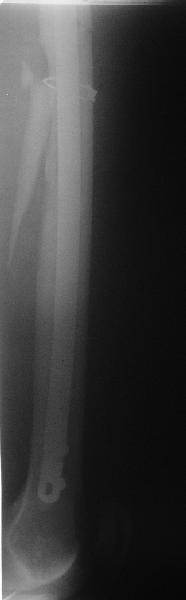

Несращение бедра

Пациент попал под наше наблюдение через 3 недели после первого остеосинтеза (фото 1). Учитывая, нестабильность остеосинтеза, выстоящий стержень закрыто перештифтовали (фото 2), через 3 месяца динамизация. К 5 месяцам имели укорочение 2 см, при том, что динамический винт стал статическим. От дальнейшей динамизации отказались, учитывая наличие контакта между фрагментами и возможность прогрессирования укорочения. К 1,5 года сращение не достигнуто (фото 3). Удалили гвоздь, выполнили дистракционный остеосинтез с целью стимуляции остеогенеза и компенсации укорочения (фото 4), потом закрыто перештифтовали после рассверливания (фото 5). На сегодняшний день, через 4 месяца после последней операции (фото 6) признаков регенерата нет, длина восстановлена, ходит без дополнительной опоры.

Возможные варианты: 1)подождать - однако регенерата не заметно 2)Снова потерять длину (динамизация, компрессирющий остеосинтез на этом гвозде, после перепроведения проксимальных винтов и копрессирующей заглушки, восстановление длины после сращения) 3)Костная пластика